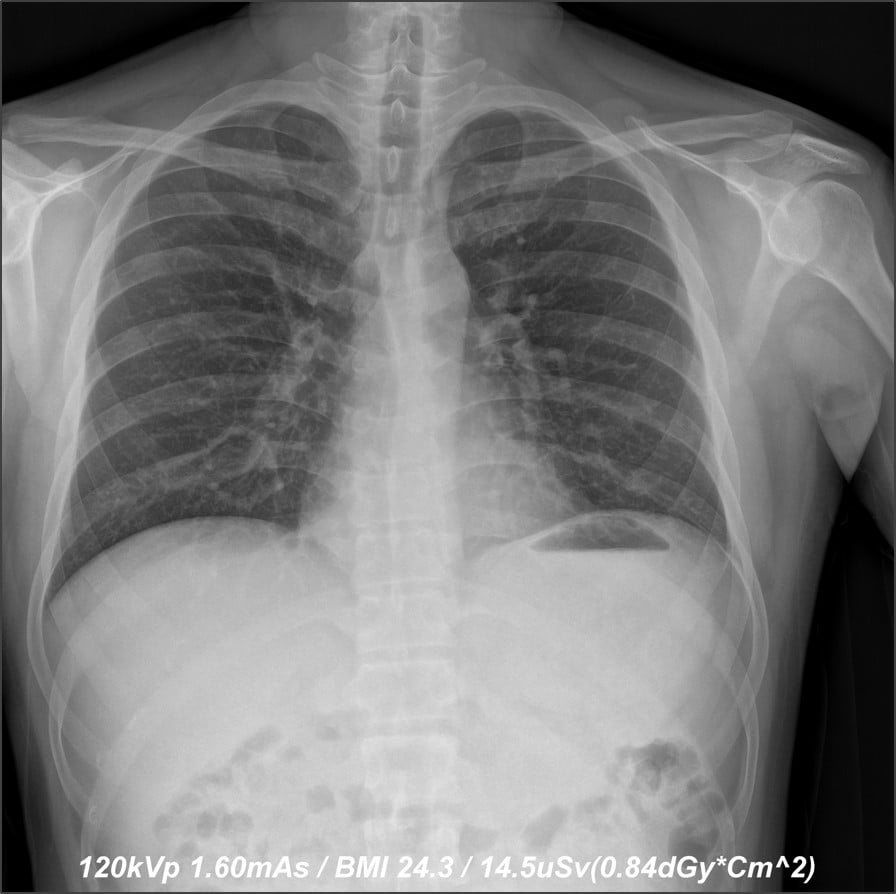

The images (before) depict a 50 percent dose reduction in chest X-ray without compromising

image quality.

When an opportunity to conduct a reduced-dose study with Samsung arose, DeAngelo and his team accepted. The 2017 study was aimed at reducing the radiation dose of adult chest X-rays by 50 percent utilizing Samsung’s GC85A digital radiography (DR) system.

“The goal in radiology, especially in diagnostic radiology, is to produce quality images with the lowest radiation dose possible,” said Hetal Patel, M.D., Greensboro Radiology PA, Chief of Radiology at Cone Health-ARMC. He noted that when applying the new Samsung algorithm, they were able to reduce the dose by 50 percent and maintain the same image quality as previous doses — or in some instances better. This approach could be applied to other areas, he explained, noting, “We are very excited about opening the possibilities for all types of diagnostic radiology.”

During the reduced-dose study, Patel evaluated 10 posterior anterior (PA) chest X-rays. Each X-ray was evaluated under three settings: H++ (sharp), M++ (medium sharpness) and S++ (soft, or similar to computed radiography [CR]). “I felt that the M++ displayed the PA chest best,” concluded Patel. “The overall image quality was excellent in all 10 instances. No X-ray had to be repeated to improve image quality.

“The degree of penetration was excellent, which was best delineated by the improved visualization of the retro-cardiac region on the PA view,” Patel continued. “The remainder of the anatomic structures was also clearly demarcated on all 10 X-rays, [as well as] the boney structures.”

Prior patient X-rays were also used in the study to compare quality. The reduced-dose X-rays were judged to be of either comparable quality or improved quality over the previously captured images. Patel believes the reduced-dose algorithm would be applicable to all types of X-ray exams, and would accomplish many radiologists’ goals of reducing radiation dose for all patients.